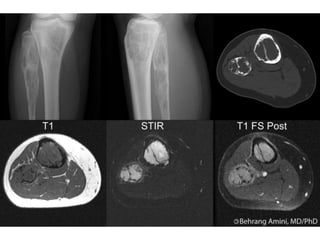

CHONDROBLASTOMA

• These are benign tumours of childhood.

• They occur most commonly at the epiphyses, usually at the ends of

long bones.

• They account for less than 1% of all bone neoplasms and are more

common in males.

• The peak age of incidence is in teenage years, rare after the age of

35 and exceptional before the age of 10.

• They typically present with pain and can occasionally cause a joint

effusion or stiffness.

• They appear as a round or oval lytic lesion ranging in size from 1 to

7 cm on X-ray.

• They appear within the epiphysis or apophysis and can cross the

physis. The cortex may be expanded but often is not breached

(Figure 9.15). MRI demonstrates a homogeneous high signal lesion.

• Histologically, they appear as ‘wet-sawdust’ with areas of chondroid

matrix, calcification and haemorrhage.

• The presence of ‘chicken-wire’ calcification is pathognomonic.

• Areas resembling an ABC may be seen in 35% of cases.

• The majority of cases can be treated with simple curettage with or

without bone grafting to the defect to support the subchondral

plate.

• Smaller lesions may be amenable to radiofrequency ablation under

CT guidance.

• Recurrence is not infrequent and can be seen in about 10% of

cases.

• Violation of the joint should be avoided to prevent contamination.

• More aggressive, en-bloc resection may be required for recurrent

disease

CHONDROBLASTOMA • These arebenign tumours of childhood. • They occur most commonly at the epiphyses, usually at the ends of long bones. • They account for less than 1% of all bone neoplasms and are more common in males. • The peak age of incidence is in teenage years, rare after the age of 35 and exceptional before the age of 10. • They typically present with pain and can occasionally cause a joint effusion or stiffness. • They appear as a round or oval lytic lesion ranging in size from 1 to 7 cm on X-ray. • They appear within the epiphysis or apophysis and can cross the physis. The cortex may be expanded but often is not breached (Figure 9.15). MRI demonstrates a homogeneous high signal lesion.

• 45.

• Histologically, theyappear as ‘wet-sawdust’ with areas of chondroid matrix, calcification and haemorrhage. • The presence of ‘chicken-wire’ calcification is pathognomonic. • Areas resembling an ABC may be seen in 35% of cases. • The majority of cases can be treated with simple curettage with or without bone grafting to the defect to support the subchondral plate. • Smaller lesions may be amenable to radiofrequency ablation under CT guidance. • Recurrence is not infrequent and can be seen in about 10% of cases. • Violation of the joint should be avoided to prevent contamination. • More aggressive, en-bloc resection may be required for recurrent disease